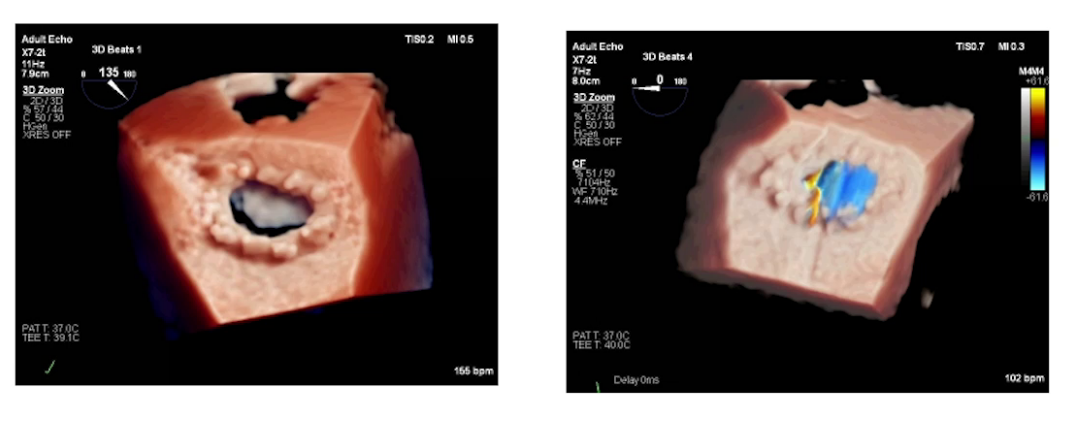

超声心动图:LVEF值低,左室流出道内径增大,主动脉瓣存在狭窄及反流,二尖瓣关闭不全,外院冠脉CAG提示前降支供血区域缺血,右冠远端100%闭塞。

3.手术过程与处理:手术进行主动脉瓣置换、二尖瓣成形及两根冠脉搭桥。体外循环时间180分钟,阻断135分钟,并行35分钟。复跳时出现缓慢节律及频发室颤,经处理后停机,停机时血流动力学指标可接受,使用多巴酚丁胺及肾上腺素维持。术后经食道超声显示主动脉瓣及二尖瓣情况改善,心功能较术前好转。但停机后30分钟发生室上性心动过速,转为房颤心律,关胸前仍为房颤节律,血流动力学参数可接受。手术入液量、出血量、尿量等数据记录完整。